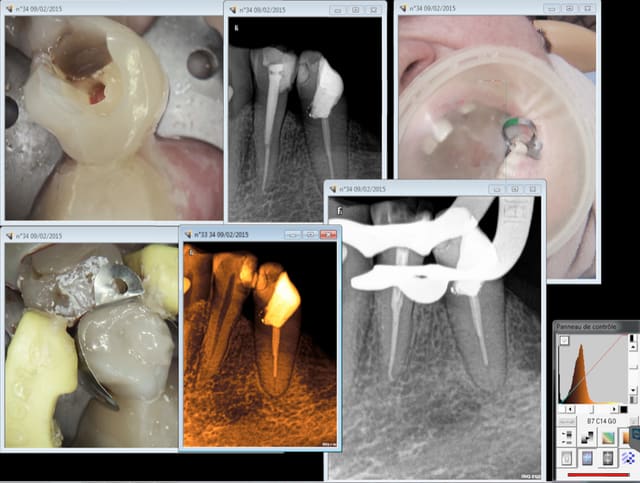

Tenon titane apol. Mais puits réalisé au largo 3 etching, adhésif puis compo apol fluide prise mixte au lentulo avant d'insérer le tenon.

Protocole néanmoins à améliorer, poser la matrice AVANTde commencer l'endo ca fait office de reconstitution pré-endo.